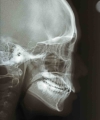

| 治療後2年経過時

|